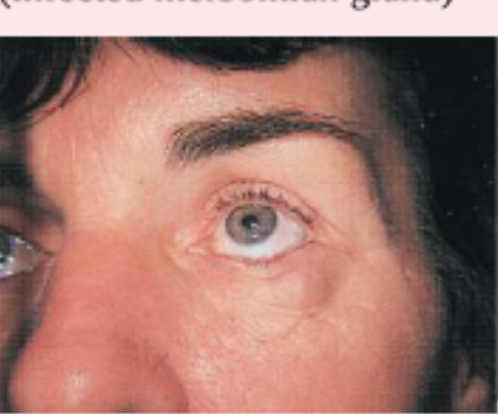

chalazion

infected meibomian gland